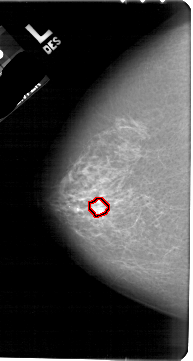

A_1534_1.LEFT_MLO

LEFT_MLO LINES 5491 PIXELS_PER_LINE 3196 BITS_PER_PIXEL 12 RESOLUTION 43.5 OVERLAY

FILE: A_1534_1.LEFT_MLO.OVERLAY

TOTAL_ABNORMALITIES 1

ABNORMALITY 1

LESION_TYPE MASS SHAPE IRREGULAR MARGINS ILL_DEFINED

ASSESSMENT 4

SUBTLETY 4

PATHOLOGY MALIGNANT

TOTAL_OUTLINES 1

BOUNDARY